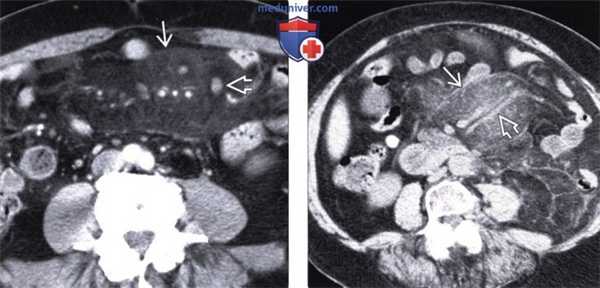

(Слева) На аксиальной КТ у пациента с болевой симптоматикой и лихорадкой определяется инфильтрация брыжейки тощей кишки, отграниченная псевдокапсулой. Визуализируются также множественные хорошо заметные брыжеечные лимфатические узлы с жировым «гало». При ПЭТ не было выявлено гиперфиксации радиофармпрепарата, симптомы регрессировали после назначения стероидной терапии.

(Справа) При аксиальной нативной КТ у пациента с длительно существующим болевым синдромом выявлена инфильтрация брыжейки тощей кишки с псевдокапсулой. Брыжеечные сосуды сдавлены, но без признаков обструкции. Все эти изменения являются проявлением и склерозирующего мезентерита.

(Слева) На аксиальной КТ с контрастным усилением определяется объемное образование брыжейки инфильтративного характера, вовлекающее брыжеечные сосуды. Обратите внимание на застойные изменения брыжеечных вен. Все это признаки склерозирующего мезентерита.

(Справа) На аксиальной КТ с контрастом у пожилой женщины с болевой симптоматикой и диареей определяется мягкотканное объемное образование в основании брыжейки тонкой кишки, окружающее и сдавливающее брыжеечные сосуды. После биопсии был подтвержден диагноз фиброзирующего мезентерита.

(Слева) На аксиальной КТ с контрастным усилением визуализируется кальцинированное объемное образование в левом верхнем квадранте брыжейки, стягивающее петли кишечника.

(Справа) На корональной КТ с контрастом у этого же пациента определяется обызвествленное объемное образование. Обратите внимание на венозные коллатерали, сформировавшиеся в результате обструкции верхней брыжеечной вены, а также диффузное утолщение стенки тонкой кишки из-за обструкции венозных/лимфатических сосудов. В данном случае изменения обусловлены гистологически подтвержденным стягивающим мезентеритом.